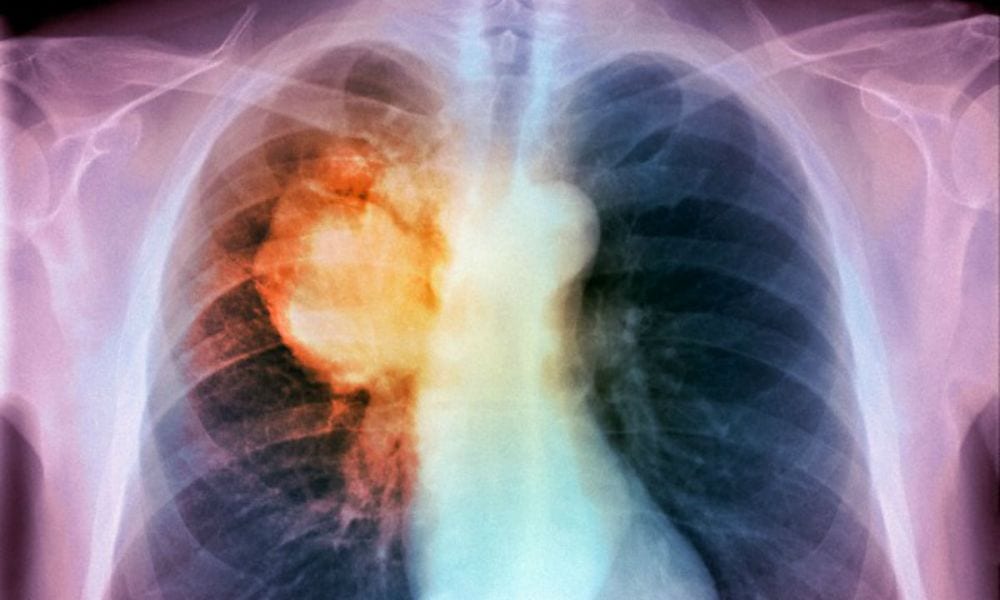

Ogni novità nella lotta al cancro è ovviamente accolta con entusiasmo, soprattutto se riesce ad evitare il ricorso alla chemio terapia. Arriva dalla Australia il via libera ad un farmaco che scioglie letteralmente le cellule cattive.

In questo periodo il dibattito tra medicina alternativa e chemioterapia è diventato più serrato che mai. Da una parte si elencano le vittime causate da cure naturali completamente inefficaci ma dall’altra non si possono ignorare nemmeno le controindicazioni della chemio. Per quanto riguarda il tumore al polmone, statisticamente uno dei più mortali in assoluto, un nuovo farmaco che arriva dall’Australia potrebbe definitivamente porre fine al dilemma. Si tratta del Keytruda, un medicinale rivoluzionario che scioglie il cancro ai polmoni evitando così la chemio. Al momento viene utilizzato per il melanoma, il tumore della pelle causato soprattutto dall’esposizione al sole, ma alcuni studi portati avanti dal Westmead Hospital di Sydney hanno dimostrato la sua efficacia anche sul ben più temibile cancro ai polmoni (LEGGI ANCHE: FUMARE IN CASA? É COME APRIRE LA PORTA AD UN SERIAL KILLER).

Il principio attivo contenuto dal Keytruda è il pembrolizumab, il quale si appoggia al sistema immunitario dell’uomo per ottenere il migliore dei risultati. L’oncologa Rina Hui ha coordinato la ricerca, portata avanti a livello mondiale, e ha affermato senza timori che si potranno dare “nuove speranze a questi pazienti“. Dopo 12 mesi il farmaco ha fermato la diffusione del tumore quasi nel 50 per cento dei pazienti. I dati lo confermano 3 volte più efficace della chemio nonostante sia stato testato su malati il cui cancro avanzato si era diffuso fuori dai polmoni e nonostante in questi si fosse manifestato un marker che dimostra il ‘travestimento’ delle cellule cancerose in cellule sane.

Questo farmaco riesce a smascherare il camuffamento permettendo così al sistema immunitario di individuare il tumore e attaccare le cellule maligne. I numeri parlano chiaro: i pazienti di cancro ai polmoni allo stadio 4 possono avere una possibilità del 70 per cento di vivere oltre 12 mesi senza bisogno di ricorrere alla chemio. Senza il Keytruda i benefici non durano a lungo mentre il farmaco, quando il malato riesce a rispondere, garantiscono una vita più lunga e sana. La svolta definitiva in questo caso sembra davvero ad un passo.